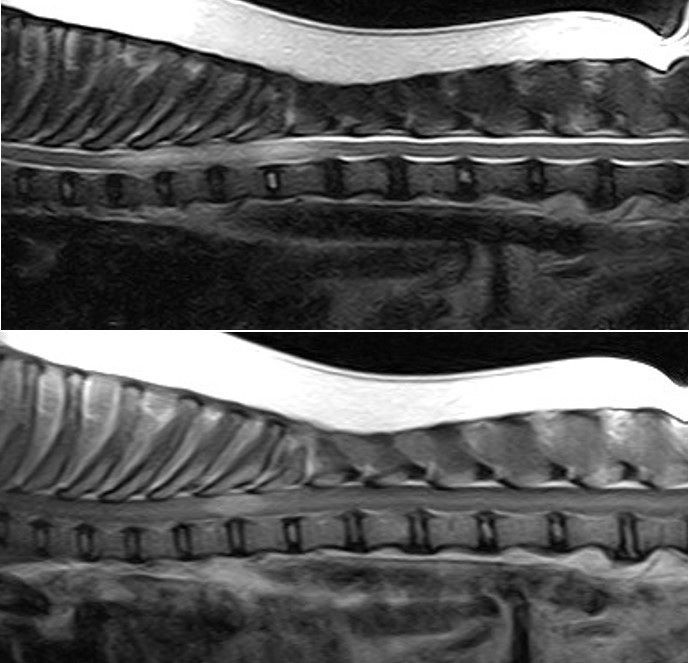

At our hospital we see cat patients after sustaining a trauma. They can have spinal fractures (Fig 1). But because cats have normally a very elastic body, they bend the spine during the trauma until the disk ruptures with a traumatic disk extrusion as consequence. The damage to the spinal cord can be severe, but in most cases a surgery would not help. The MRI is the only diagnostic tool to clearly diagnose such a traumatic extrusion (Fig 2). Fractures to the sacrum and the first vertebra of the tail are also typical for cats. The nerves to the bladder are often damaged in these patients, so the cat has to be in the hospital to ensure the treatment of bladder and fracture (Fig 3).

Fig 1 Fig 2

Fig 1 Fig 2